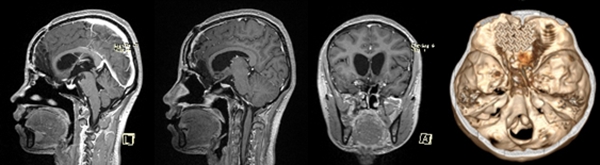

從術后磁共振和CT檢查看到,腫瘤已經被全切,腦組織恢復很完美,顱底使用鈦板修復。重慶醫科大學附屬第二醫院供圖